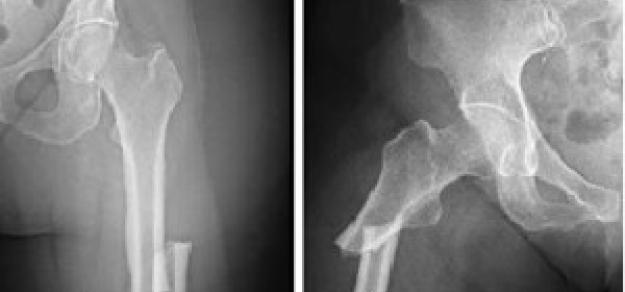

Combinaciones de implantes de elección en reemplazo total de cadera

09 noviembre 2017

BMJ, 2 de noviembre de 2017 Las combinaciones de implantes más recientes no fueron mejores que la combinación de implantes de referencia en términos de riesgo de cirugía de revisión o la puntuación Harris de cadera.